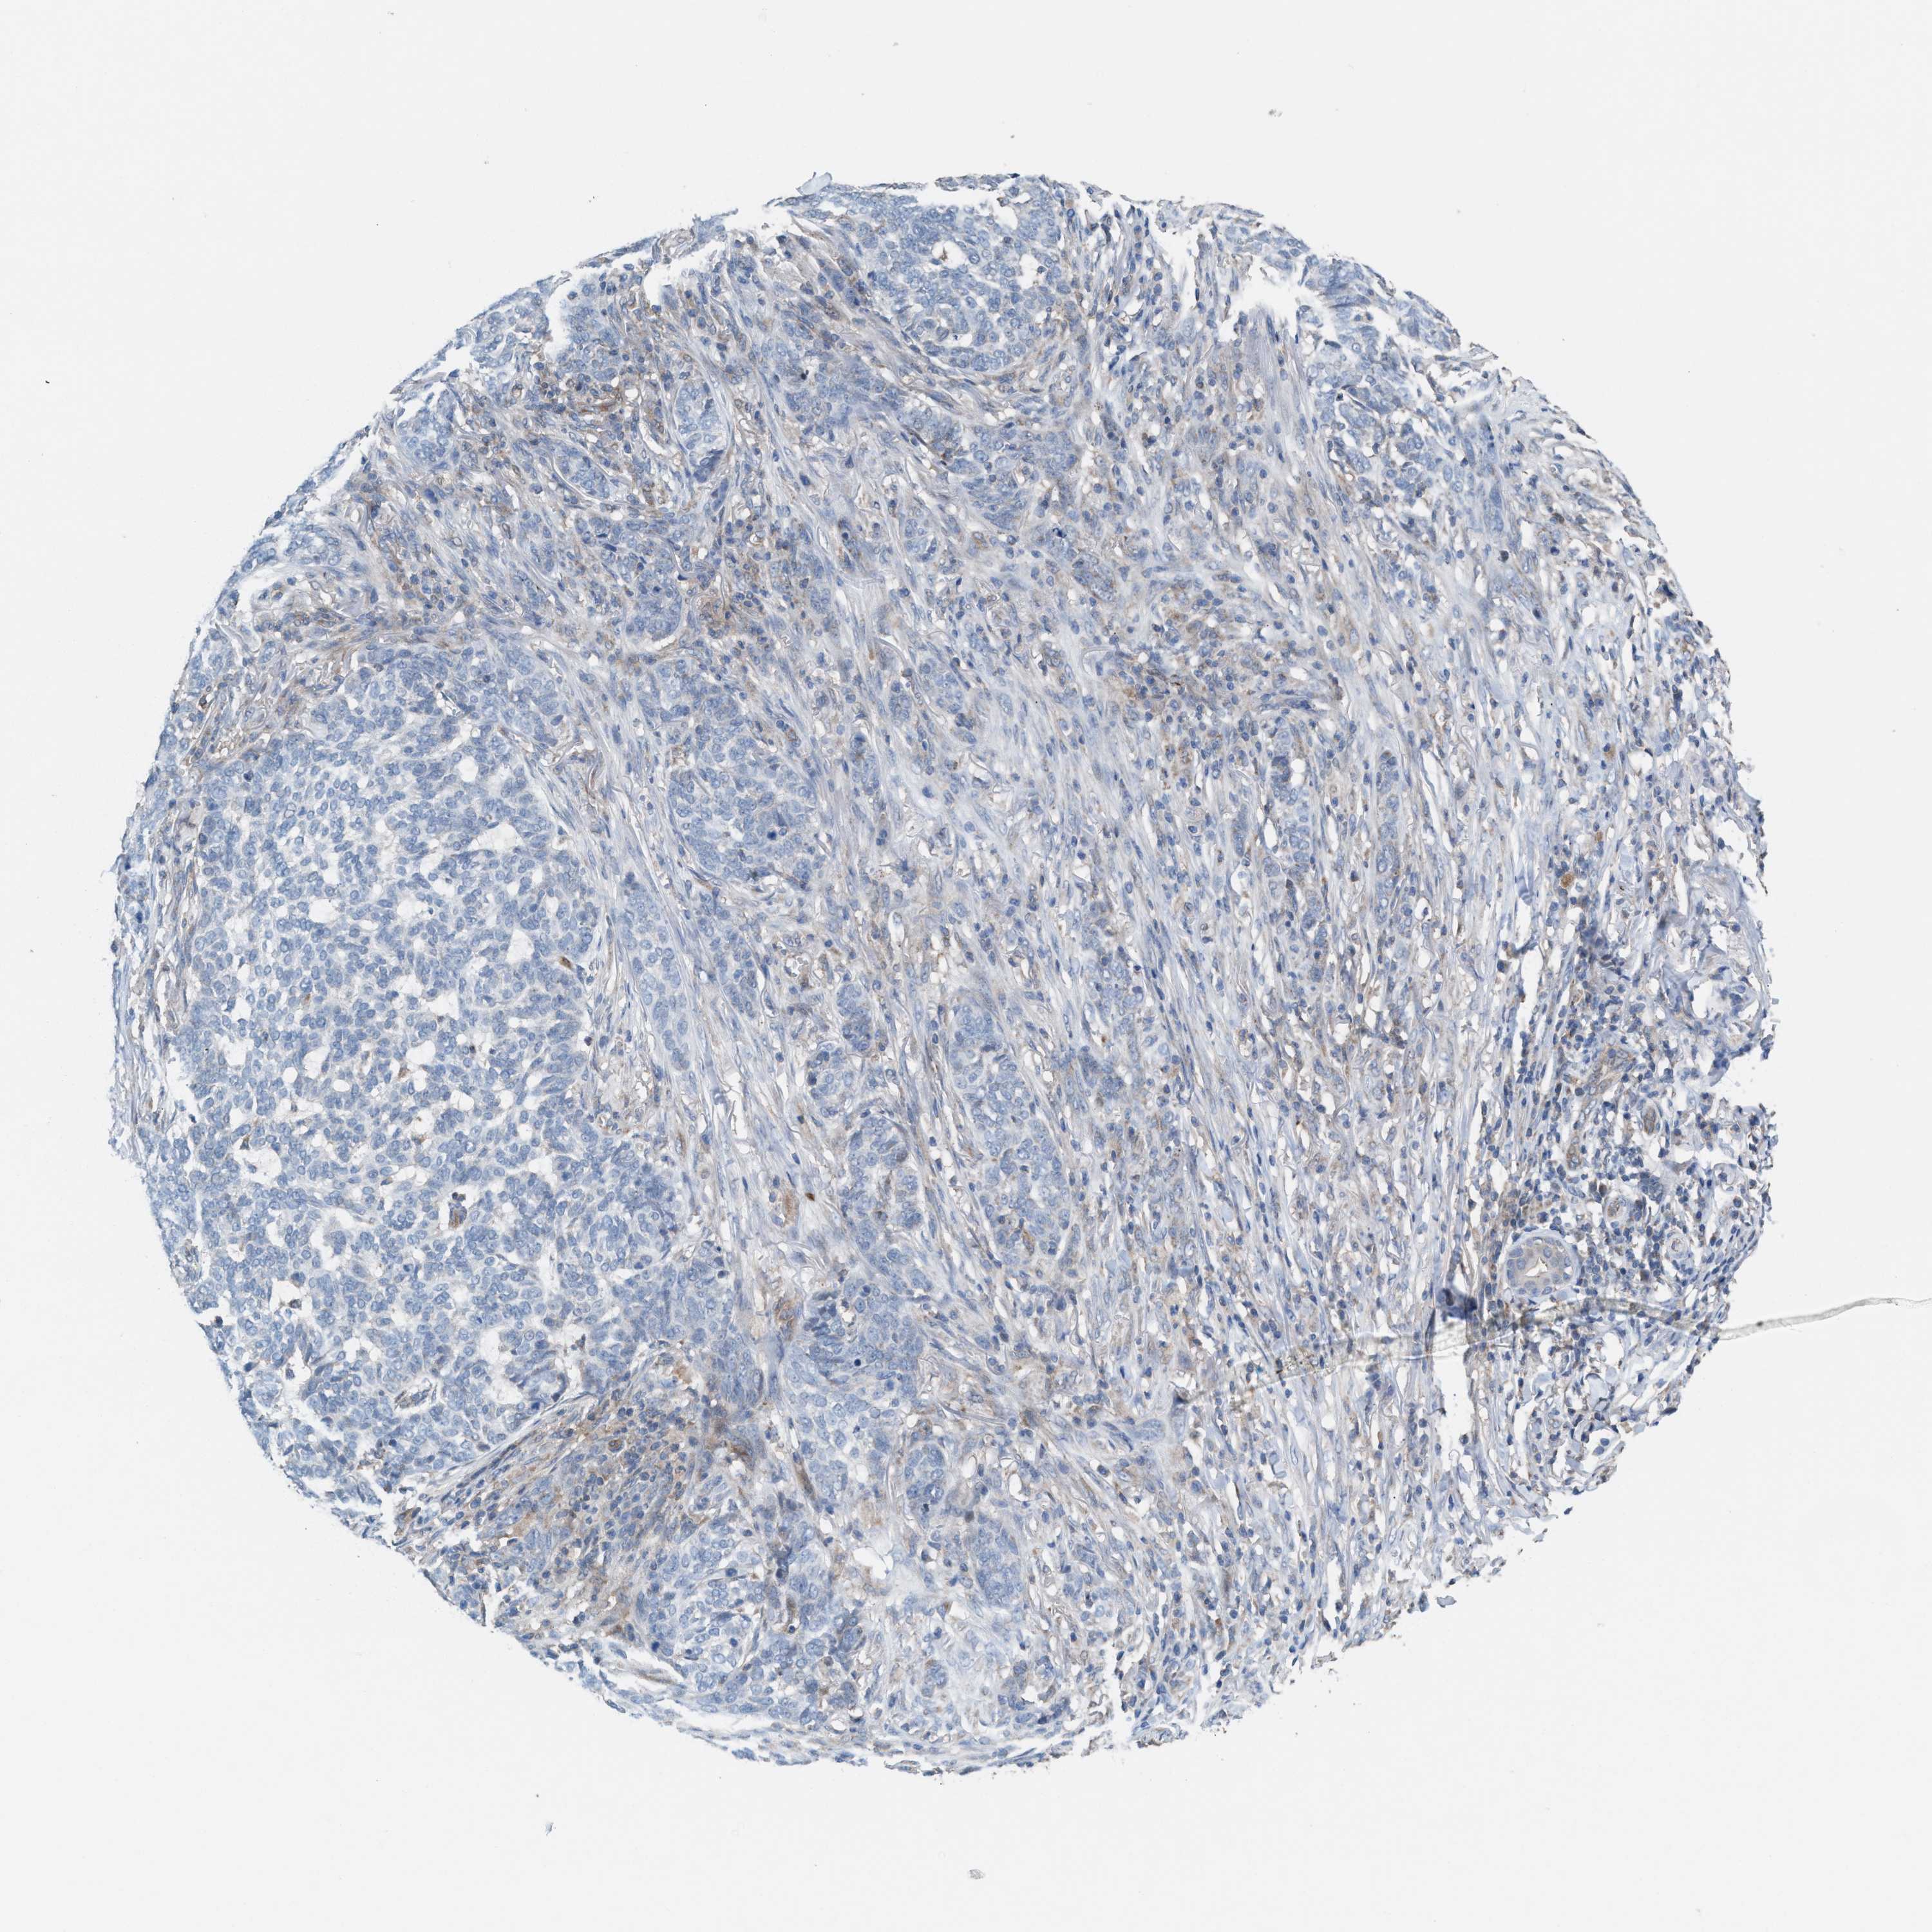

SKIN CANCER - Protein expressioni

A mouse-over function shows sample information and annotation data. Click on an image to view it in a full screen mode. Samples can be filtered based on level of antibody staining by selecting one or several of the following categories: high, medium, low and not detected. The assay and annotation is described here.

Each image is clickable and will lead to virtual microscopy that enables deeper exploration of all samples and also displays staining intensity scores, fraction scores and subcellular localization as well as patient and tissue information for each sample.

Antibody HPA021598

Squamous cell carcinoma in situ, NOS

Squamous cell carcinoma, NOS

Squamous cell carcinoma, metastatic, NOS

Basal cell carcinoma

Adnexal tumor, benign